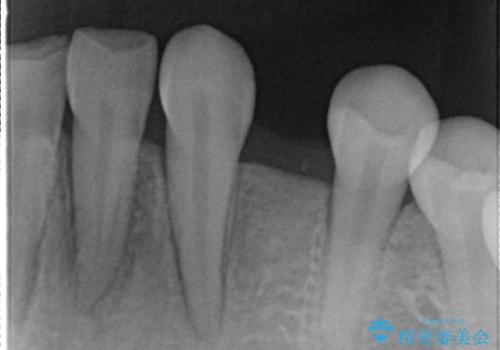

- 左下の歯が生まれつき無かった患者様です。

矯正治療にてスペースを一箇所に集めてからオールセラミックブリッジにて補綴治療を行いました。

今回は、患者様の希望もありインプラントではなくブリッジにて修復しています。